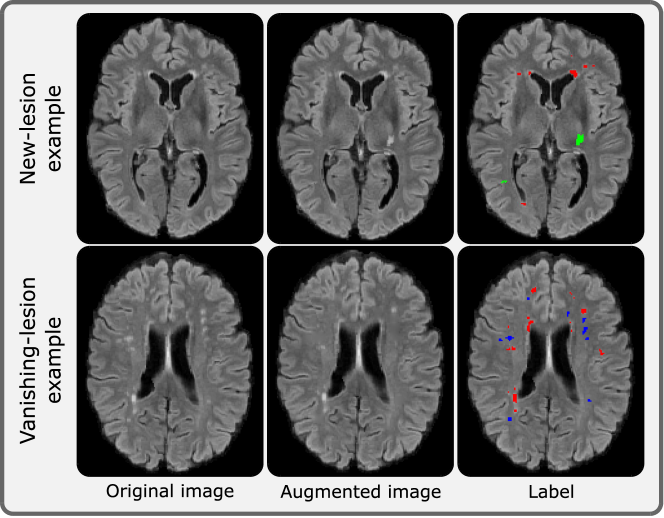

LesionMix was originally proposed for augmenting cross-sectional brain images. Here we employ it to augment both cross-sectional and longitudinal brain images. LesionMix complements SegHeD+ in three manners. First, it can generate both new lesions and vanishing lesions, thus increasing the diversity of the the various labels SegHeD+ can analyse in heterogeneous datasets. This both increases dataset variance, and reduces the effect of label imbalances which may occur from one type (new lesions) appearing more than another one (vanishing lesions). Second, its lesion populating and inpainting strategy along with lesion mask output allows for synthetic generation of longitudinal data. Lesions can be populated at the second timepoint as new lesions, or inpainted as vanishing lesions. Finally, LesionMix operates by populating or inpainting lesions to a predetermined lesion load, thus can control lesion volume for augmented images [9]. By integrating LesionMix with the volumetric constraint knowledge and uniformly sampling between the lesion volume increase and decrease thresholds, αhigh\alpha_{high} and αlow\alpha_{low}, we set a target load for an image, and augment it to generate an augmented second timepoint. We refer the reader to  [9] for more implementation details of LesionMix. Here, we present example outputs of LesionMix augmentation in Figure 2.

Figure 2: Example outputs of LesionMix augmentation. Red labels denote lesions which are present in the original image; green labels denote new-lesion generated in the augmented image; blue labels denote vanishing-lesions which have been inpainted from the original image. Images best viewed online.